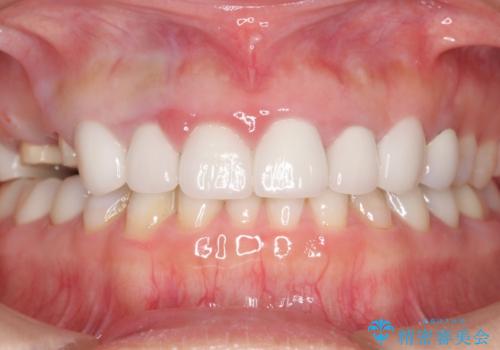

かぶせものと歯ぐきの境目が黒い 40代女性

- 被せ物と歯ぐきの境目が黒いことを気にされ、来院された患者様です。

精査したところ、メタルボンドクラウンの金属部分が露出し黒く見えていました。

患者様のご希望により、金属を使わないオールセラミックのブリッジによる補綴治療を行いました。

自然な仕上がりと咬み心地に喜んで頂けました。